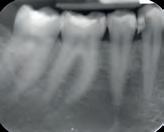

Bij deze patiënte was gebitselement 36 erg pijnlijk en had een extreem pijnlijk reactie op een koudetest. Patiënte was al even niet meer bij de tandarts geweest en had al twee dagen niet kunnen slapen van de kiespijn. Op de röntgenfoto (afbeelding 1) is onder andere te zien dat gebitselement 36 een diepe restauratie heeft, de restauratie van gebitselement 37 secundaire cariës toont en dat er distaal van de 37 een forse brok subgingivaal tandsteen aanwezig is. Er is geen duidelijk periapicaal granuloom

te zien en dat maakt dat de diagnose een irreversibele pulpitis is. Het plan was om een pulpotomie te doen.

Afbeelding 1. Gebitselement 36 heeft een diepe restauratie en er is, secundaire cariës mesiaal van de 37 (en een forse brok subgingivaal tandsteen). Er is geen duidelijk periapicaal granuloom te zien. Let op de morfologie van de mesiale radix, hier lijkt in retrospect een aanwijzing voor een mid-mesiaal kanaal.